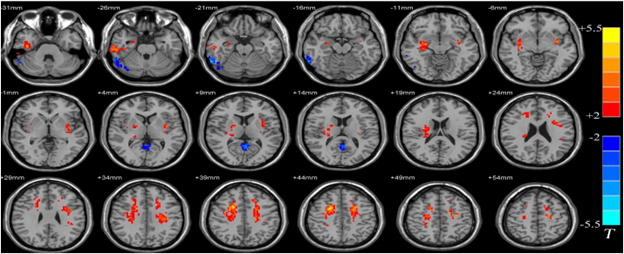

In “Postphenomenological variation of instrumental realism on the problem of representation: fMRI imaging technology and visual representations of the human brain,” Dmytro Mykhailov aims to provide

an alternative answer to the ‘problem of representation’ from the perspective of instrumental realism. The ‘problem of representation’ frames a significant part of the debates in the contemporary philosophy of science. Two extreme answers to this problem are from realist and constructivist accounts. Realists insist that any scientific representation relies on (and refers to) independent reality. Constructivists, on the contrary, insist that through representational devices, scientists ‘construct’ what is real. In his paper, Mykhailov shows that there is another possible perspective on the ‘problem of representation.’ This perspective has been brought into play by instrumental realism. Mykhailov takes findings from the postphenomenological variation of instrumental realism and develops an ‘environmental framework’ to give a philosophical answer to the problem of representation through the use of imaginaries taken into consideration by science fiction. The framework focuses on three elements of the representational environment? image-making technology, image as a representational device, and scientific hermeneutic strategies occurring within the image interpretation process in the laboratory set-up. The central idea is that scientific images do not produce meanings without their instrumental environment. To fulfill this idea with empirical consistency, Mykhailov applies the ‘environmental framework’ to contemporary debates on fMRI imaging technology. Within the last decade, fMRI technology has attracted the attention of scholars from different fields. Such an increasing interest was called forth by the revolutionary impact that fMRI had on almost every part of neuroscientific research. However, fMRI technology images have a peculiar nature. On the one hand, fMRI technology images are not ‘mere’ representations because they are not just a ‘copy’ of the human brain, while on the other hand, these images are often used as representational devices within medical diagnostics. Mykhailov shows that the ‘environmental framework’ can help better understand the problematic nature of the fMRI by explaining how fMRI visuals receive their meaning through the interplay between different elements of the instrumental environment.